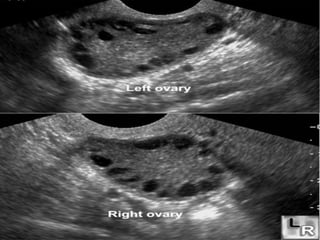

Follicular cyst A-right ovary, B-left ovary.

A B Follicular cystA-right ovary, B-left ovary.